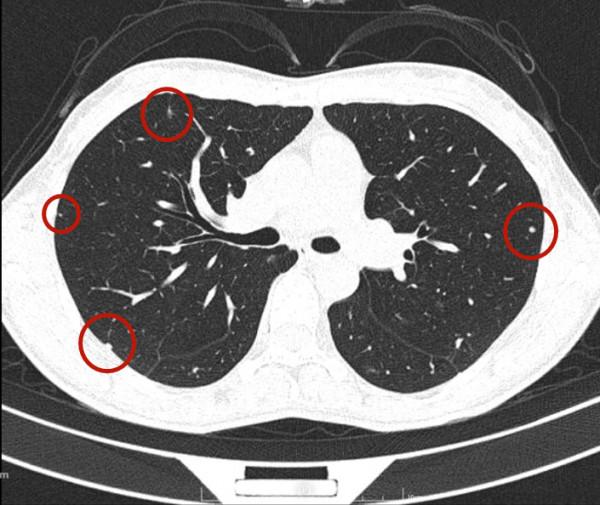

今天一位網路問診病人,女性,34歲,檢查發現雙肺多發實性結節,在當地醫院不同科室就診意見不一,再到不同醫院胸外科就診,意見也不一。怎麼辦呢?是結核、免疫疾病、風溼,還是腫瘤轉移?要不要手術活檢?我們來瞧瞧她的病例:

可見她體檢發現,沒有症狀,看了呼吸科、風溼免疫科、結核科以及胸外科,而且還看了三家三甲醫院的胸外科,但意見莫衷一是。其CT是如何的呢?來看看:

那麼多結節,基本上都是實性,分佈兩肺,形態不似圓形或類圓形的轉移瘤。是什麼呢?我們是不是一定要弄明白到底是什麼病?其實我覺得有時並不一定要弄清楚,所以我回復的意見如下:我認為我們看病,有時候可以從結果來反推,從而考慮是不是干預治療。比如這個病例的兩肺多髮結節,我看沒有一個是主病灶,也就是說“明顯考慮惡性的,其他考慮是這個病灶轉移的”這種樣子。那麼這些實性小結節,可能是:1、良性結節:包括慢性炎,纖維增生、肺內淋巴結、風溼結節、肉芽腫、隱球菌等各種可能性。但只要是良性,不處理不影響生命,也沒什麼不舒服,只需關注著,定期複查就可以了;2、腫瘤多發轉移:不管原發灶在哪裡,如果兩肺這麼多轉移,你再怎麼治療,預後也不好,現在還不是典型的腫瘤,也未見明顯的原發部位,遲點有進展再考慮又有多少區別呢?3、結核:即使真是結核,沒有明顯症狀的情況下,很多人自己得過結核也不自知,意思是說,如果痰找結核菌陰性,不是活動性肺結核,沒有症狀,不治療也沒什麼關係,也是隻需要定期複查。所以你的病例,我的意見是:1、形態數目不像惡性;2、不需深究到底是什麼;3、把診斷交給時間來決定,建議每4-6個月複查平掃,有變化時展再考慮活檢或干預,否則先不去管它。